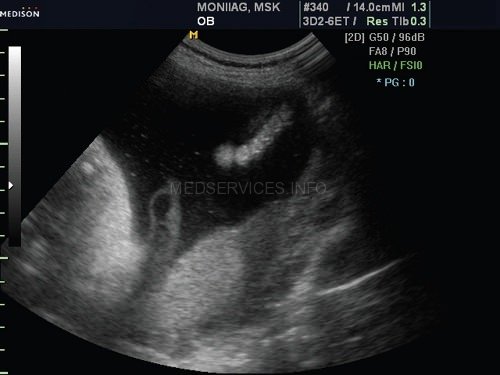

При эхографии в 37 нед беременности на фоне многоводия был обнаружен один живой плод мужского пола с аномальным внешним видом. Все длинные трубчатые кости были укорочены и соответствовали 26 нед гестации (рис. 1).

Грудная клетка была гипоплазирована. Ее размеры резко диссоциировали с размерами живота плода (рис. 2, 3).